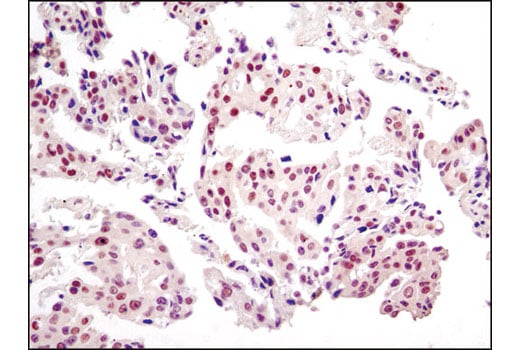

Immunohistochemical analysis of paraffin-embedded human lung carcinoma using JMJD2A (C37E5) Rabbit mAb.

Immunohistochemistry Image 1: JMJD2A (C37E5) Rabbit Monoclonal Antibody